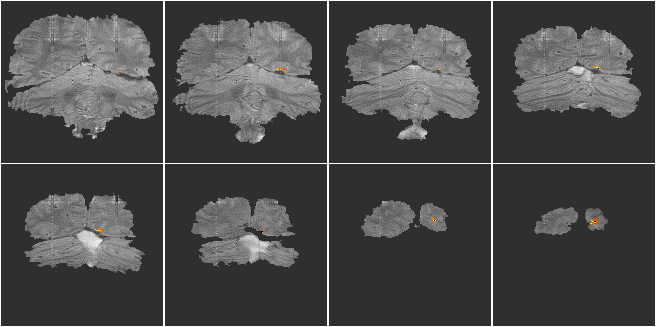

A single shot EPI, functional imaging experiment was performed using a matrix size of 128 x 64, and a switching rate of 1.04 kHz. The activation paradigm consisted of 16 seconds of viewing a flashing LED display, and pressing a hand held button at the same rate, followed by 16 seconds of rest, repeated 16 times. The visual cortex was scanned in eight slices, every 2 seconds (resolution 3 x 3 x 9 mm3). Following the activation experiment, the switched and broadening gradient strengths were doubled and four volume images of the same slices were obtained using a two shot interleaved EPI sequence, having twice the in-plane resolution (1.5 x 1.5 mm2). These were used as background images for the activation maps to be overlaid upon. The activation maps were interpolated up to twice their size, and registered to the high resolution images. The activation images are shown in Figure 5.15.

Figure 5.15 Low resolution activation images (3 x 3 mm2 in-plane) for a visual stimuli, overlaid on high resolution (1.5 x 1.5 mm2 in-plane) background T2* weighted images.